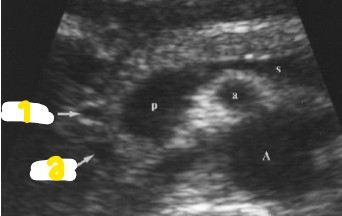

Label the structures with the colored arrows/circle.

Red = GDA

Orange = CBD

Yellow = Portal confluence

Green = Splenic vein

Blue = Uncinate process

Purple = IVC

Pink = RRA

White = LRV